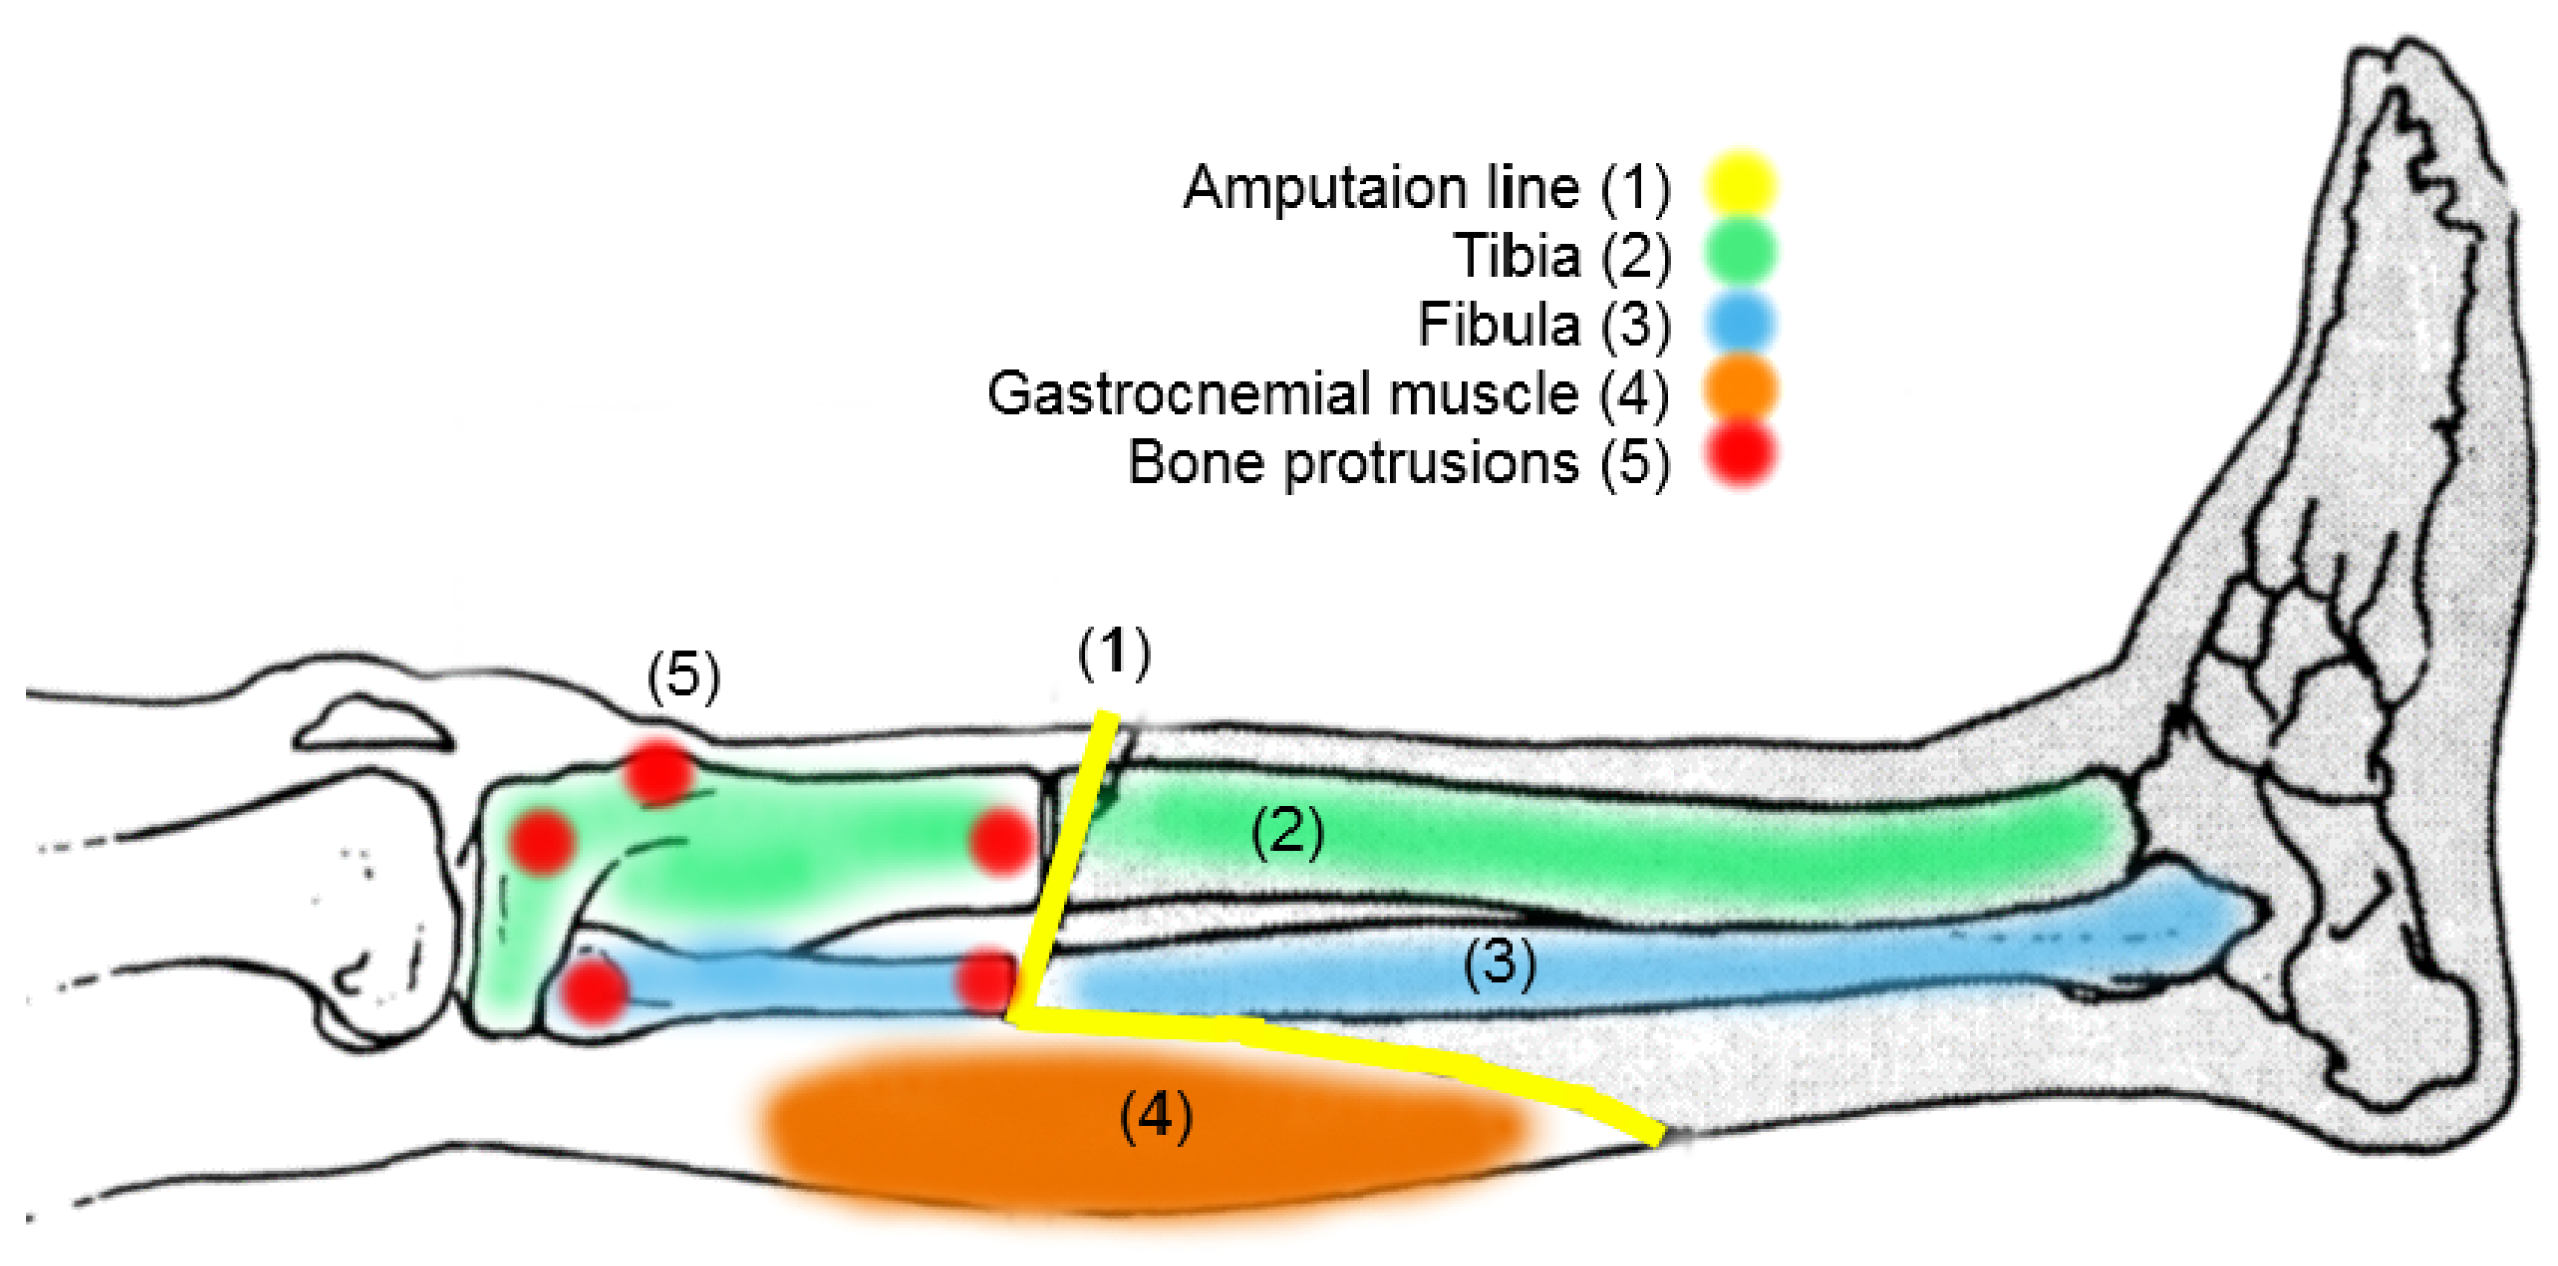

2.3. Croi Location